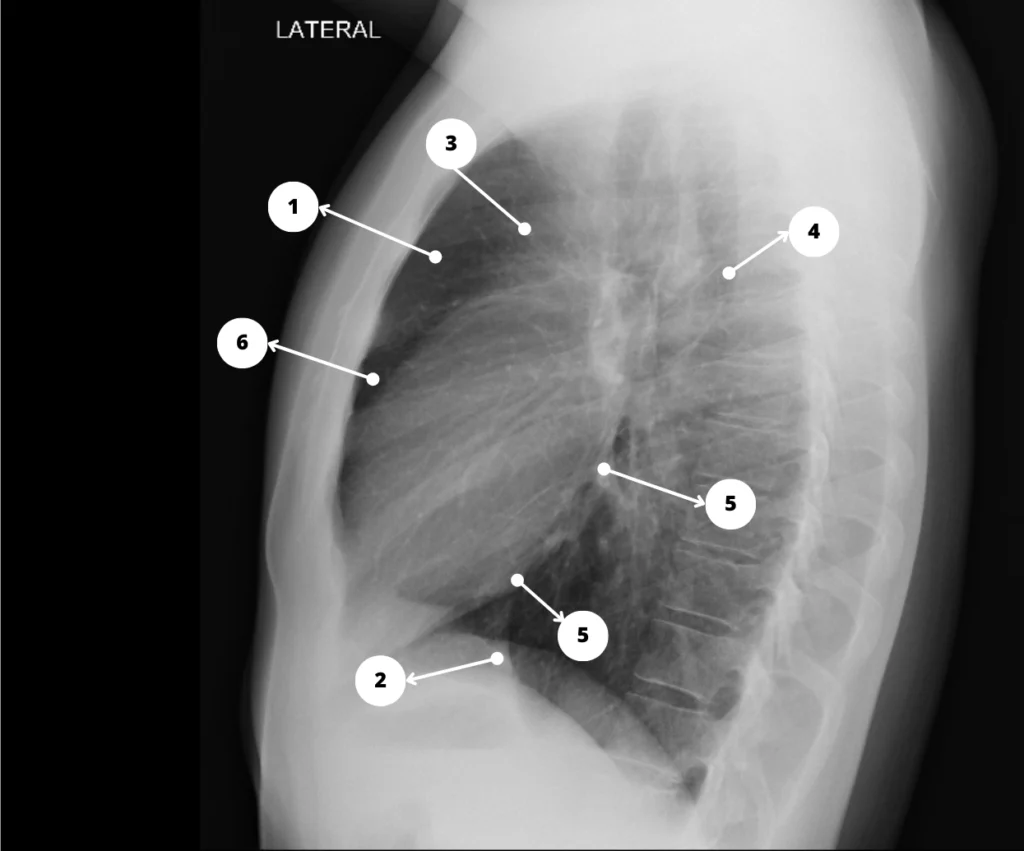

Rx de tórax lateral. Silueta cardiovascular. 1. Espacio claro retroesternal; 2. Ventrículo derecho; 3. Aorta ascendente; 4. Aorta descendente; 5. Aurícula izquierda; 6. Ventrículo izquierdo; 7. Vena cava inferior.

Radiografías de tórax normal en proyecciones PA y lateral de un paciente que concurre a un chequeo de salud. Se señalaron con números los contornos de la silueta cardiovascular, referenciando las estructuras que representan.

En la sistemática de lectura del tórax es importante evaluar los bordes de la silueta cardiovascular (C = Cardiovascular), que representan al corazón y los grandes vasos del mediastino.

Cualquier modificación en uno de estos arcos de la silueta cardiovascular puede ser un signo de patología. Por ejemplo, un arco cardiaco medio (izquierdo) prominente se observa en pacientes con hipertensión de la arteria pulmonar.

Los arcos que representan a las cámaras cardíacas se hacen prominentes cuando aumenta el volumen de la cavidad en cuestión.